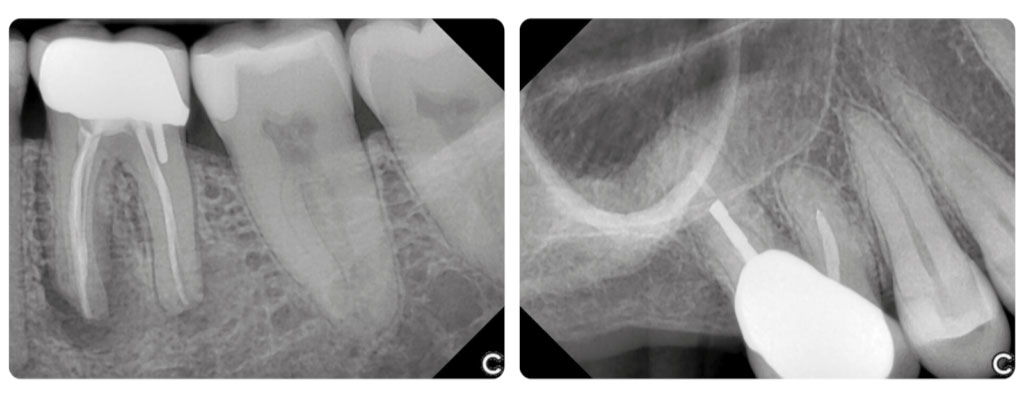

Идеальное изображение с новыми контрастными фильтрами

EzSensor Classic оснащен набором предустановленных фильтров контрастности. Это позволяет врачу адаптировать изображения под разные задачи — эндодонтию, терапевтическое лечение, реставрацию зубов и другие направления.

Благодаря точной передаче деталей и возможности настройки, стоматолог получает оптимальные снимки для диагностики и планирования лечения, независимо от сложности клинического случая

Достоверные изображения для точной диагностики

Аппарат радиовизиографический EzSensor Classic обеспечивает достоверные и стабильные снимки благодаря чувствительной сенсорной технологии. Сенсор работает с широким диапазоном экспозиций, включая совместимость со старыми рентгеновскими аппаратами.

Ключевым преимуществом является высокая контрастность изображения, позволяющая детально рассматривать зубные ткани и обнаруживать скрытые межзубные кариесы. Такой уровень точности помогает стоматологам повышать качество диагностики и результативность лечения.